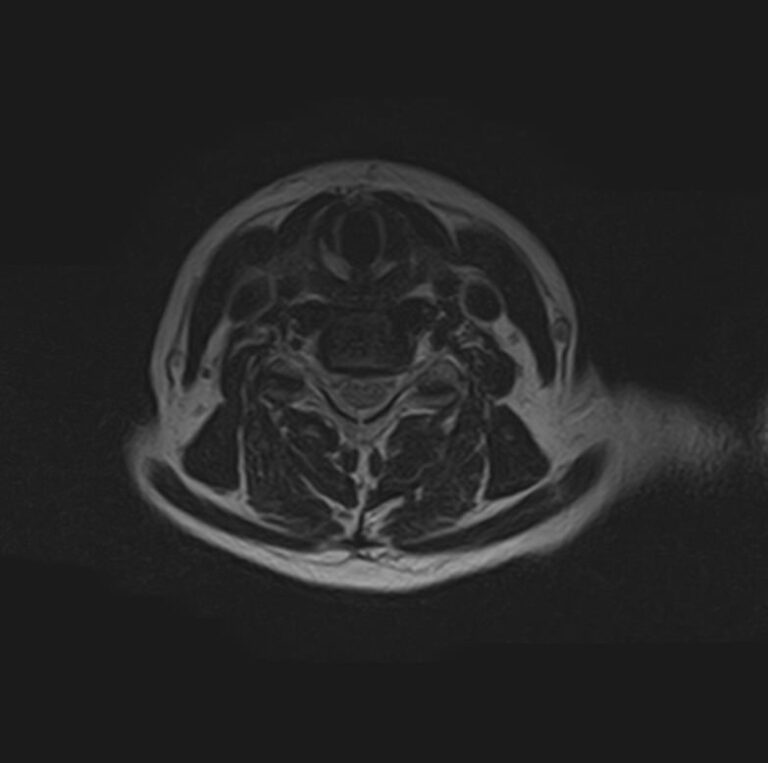

Для диагностики заболеваний ЦНС в клинике «Доступная медицина» проводится комплексное обследование МРТ ЦНС (центральной нервной системы). Клиника укомплектована высокотехнологичным оборудованием, в частности, новейшим 32-канальным высокопольным томографом TOSHIBA VANTAGE TITAN 1,5 Тесла с высокой разрешающей способностью для точной диагностики заболеваний центральной нервной системы.

МРТ центральной нервной системы (ЦНС) (головной мозг + 3 отдела позвоночника)

13 400 / 12 200 руб

Подробнее